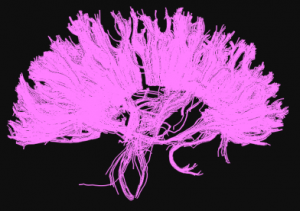

Tractografía. Técnica neurorradiológica aplicada al estudio de la neuroanatomía

Juan José Delgado Moraleda. Estudiante de Medicina en la Universidad de Valencia (España).

La tractografía es una nueva técnica de

neuroimagen que deriva de la resonancia magnética. Por medio de técnicas

no invasivas, permite obtener información de la organización de la

sustancia blanca en el cerebro humano. En el trabajo que presentamos se

utiliza la tractografía para elaborar un pequeño atlas en el que

resultan evidentes algunas de las principales vías de conexión.